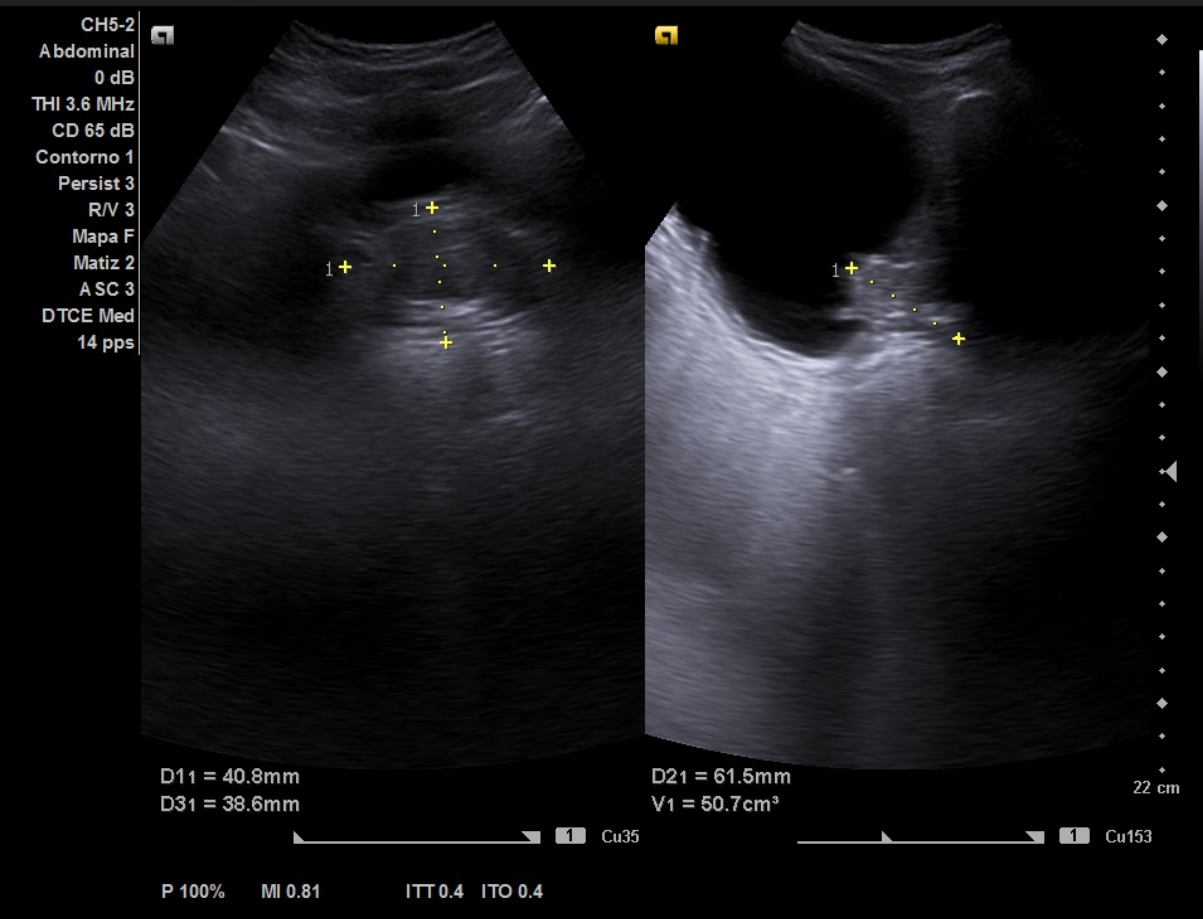

Ecografía aparato urinario en Centro de Salud: Riñones de tamaño normal, parénquima conservado con dilatación pielocalicial grado II-III izquierdo y grado II derecho. Vejiga con aspecto trabeculado, pared irregular con divertículos. Volumen premiccional 550 cc, postmiccional 450 cc. Volumen prostático de 50 cc.